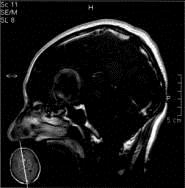

问题 病历摘要:??患者男性,56岁,因右侧视力下降伴视野缺损2个月来院就诊,诉头痛,无明显头晕,无视物重影,无恶心呕吐,无肢体抽搐,无肢体乏力,胃纳佳,大小便正常,既往史无特殊,入院检查:神志清楚,言语清楚,体毛分布正常,左侧视力4.6,右侧视力4.0,粗侧右颞侧视野缺损,左侧正常,颈软,四肢肌张力正常,肌力正常,病理征(-)。 巨型动脉瘤根据瘤腔内血栓的多少如何正确分型?

选项 A.小部分血栓形成 B.大部分血栓形成 C.部分血栓形成 D.不完全血栓形成 E.完全血栓形成 F.无血栓形成

答案 CEF